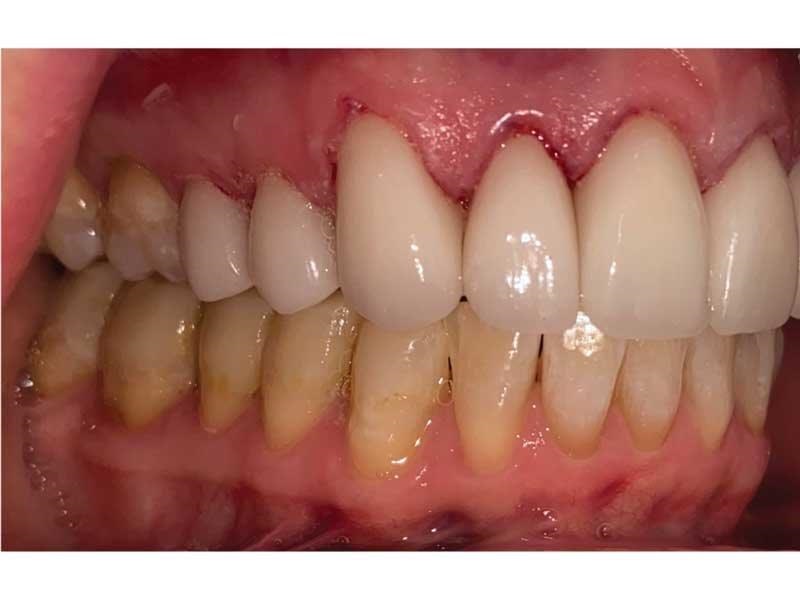

Meet Lorraine, who came into my office to “redo her bonding.” Lorraine had some upper anterior teeth done years ago with resin, which now was dull, stained and breaking down (Figs. 1–3). She had an amount of money in mind that she thought it would cost. She was very wrong.

The big challenge: Retruded and overclosed. Lorraine looked retruded and overclosed, so I started to ask her about headaches, jaw issues and chronic pain. As we talked, she revealed that she had been in severe pain her whole life. She had all the signs and symptoms of TMD and had been to multiple doctors, pain clinics, alternative medicine practitioners, massage therapists, chiropractors, osteopaths … you name it.

She told me she had just finished orthodontics and was not interested in more. She also did not want surgery, but when I suggested I could help her with her chronic pain in addition to doing her veneers, she didn’t know whether to talk about it or not because she had lost hope. So where do you go from here?